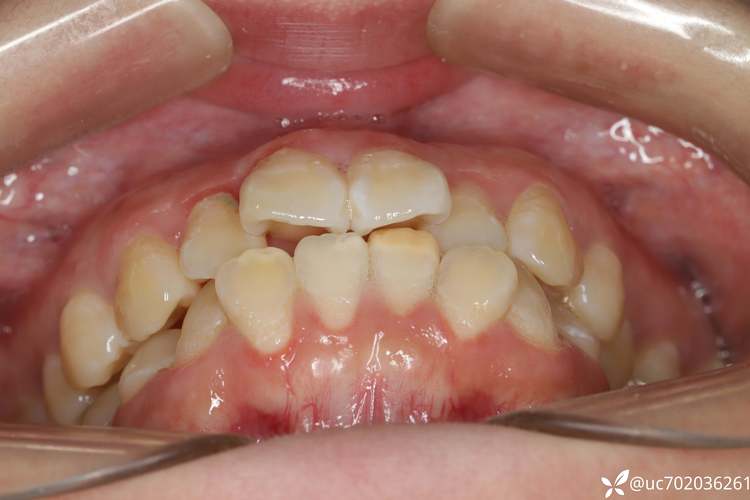

牙齿严重拥挤,牙弓空间不足

这是拔6号牙最常见的原因,部分患者天生牙弓长度较短,或因遗传、不良习惯(如吮指、口呼吸)导致牙弓发育不足,加上牙齿本身宽度较大,就会出现“牙齿挤成一团”的情况,上下颌牙弓内可容纳28颗牙齿(智齿除外),但实际空间可能只能容纳24颗,多出的4颗牙齿便会造成拥挤,拔除上下左右各一颗6号牙(共4颗),可释放约8-10mm的牙弓空间,让拥挤的牙齿排列整齐。